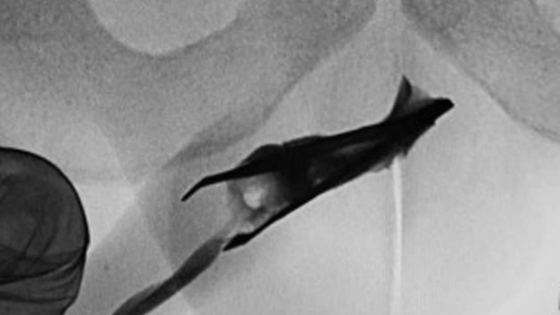

Сначала медики сделали рентген. Выяснилось, что кончик металлического предмета находится недалеко от головки органа. Это был очень острый пинцет и его концы оказались раскрыты, поэтому перед врачами стояла непростая задача. Важно было не повредить уретру.

Целый час хирурги медленно и аккуратно «проталкивали» инородное тело к «выходу». Они старались поддерживать пинцет в закрытом состоянии, для чего давили на края органа. Затем его вытащили с помощью хирургических щипцов.